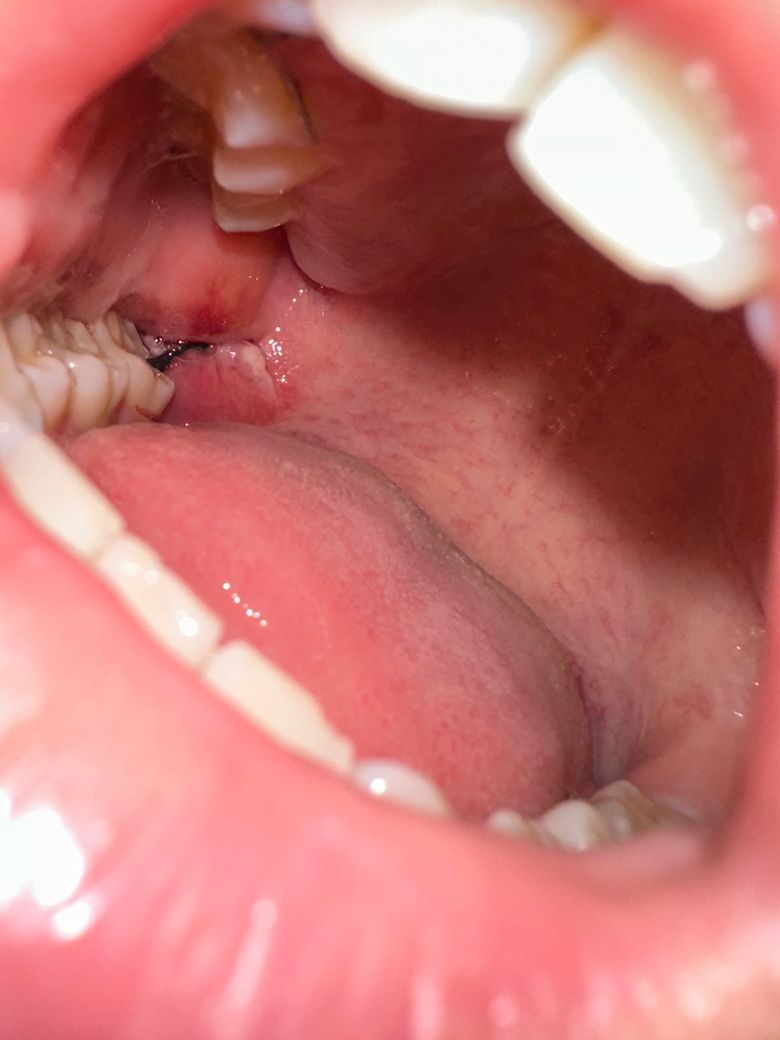

자고 일어났더니 볼 안쪽이 씹혔는지 붉은 염증이 나면서 부었어요 정상인가요? 3일차인데 붓기는 언제부터 빠질까요 ㅠㅜㅜㅜㅜㅜㅜ

발치 후 약간의 부종은 있을 수 있습니다. 보통 부종은 발치 후 3~5일차까지 지속되고, 얼음찜질 잘해주시면 금방 가라앉습니다.